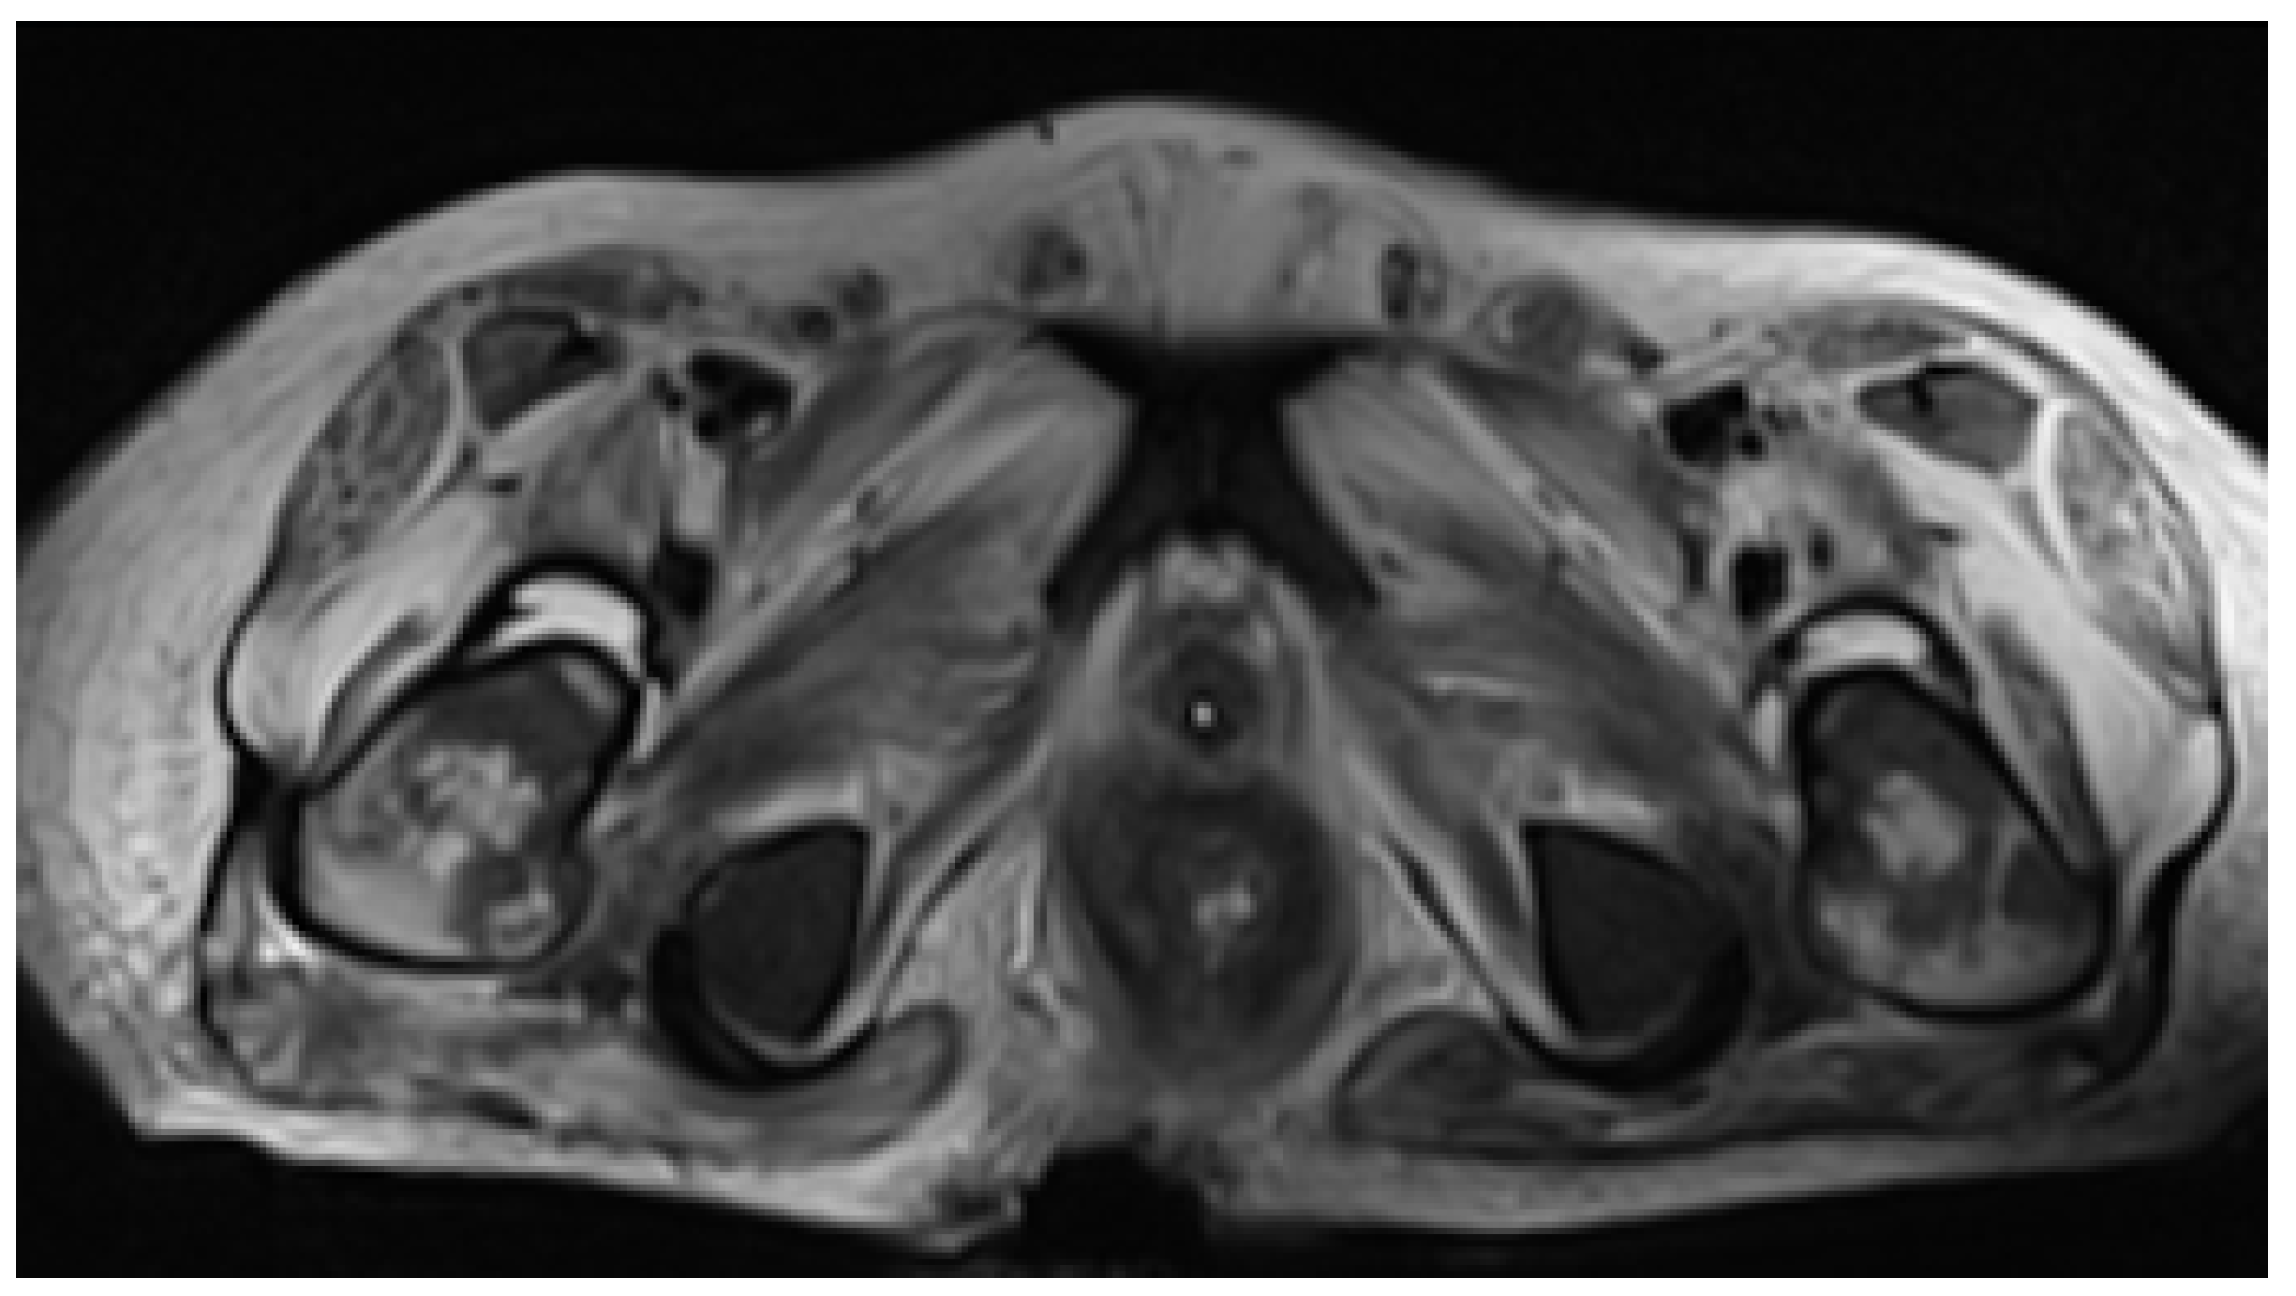

Despite being on ARV therapy since day +46 as previously mentioned, during an approximate three-week interval, HIV viral load increased from 36,904 (day +9) to 795,000 copies/mL (day +68). Additionally, on D6 of oral tecovirimat therapy, there was progression of skin ulcerations and extensive destruction of the perineum and gluteal region, with evidence of fistulization to rectum and prostate on abdominopelvic CT. For this reason, a protective colostomy was performed on day +73 to prevent contamination of the perineal lesions and allow for cicatrization to occur. In addition, CT scan showed jejunal and colic increased mucosal contrast uptake, suggesting enterocolitis (Figure 3). These facts raised concerns about probable insufficient enteric absorption of ART and tecovirimat considering the progressive gastric content stasis and enterocolitis documented on CT and therefore possible extension of inflammatory process to small bowel. This situation prompted the search of a parenteral option to both medications. On day +73 intravenous (IV), cidofovir (5 mg/kg once weekly for 2 weeks, then once every other week, following WHO interim guidance June 2022) was added to oral tecovirimat (which completed 21 days) as antiviral therapy for mpox. HIV viral load increased to 5,000,000 copies/mL, and TCD4+ dropped to 38/μL on day +75, and there was confirmation of no other mutation than M184V in contemporary resistance testing along with no mutations detected for the integrase gene. Together with viral enteropathy—the tissue had abundant inflammatory cell infiltrate and villous atrophy—reported in duodenal biopsy on day +86, which was also PCR-positive for mpox, confirmed the likely lack of absorption of oral BIC/TAF/FTC. A full parenteral regimen with intramuscular (IM) cabotegravir (CAB) and IM rilpivirine (RPV) was started on day +95, both to be administered monthly, with initial dosing of 600 mg of CAB and 900 mg of RPV together with IV zidovudine 50 mg every four hours. Six days after the initiation of the later regimen, there was already a decrease in HIV viral load from 5,000,000 to 9010 copies/mL (Table 1).

Despite therapeutic measures, clinical deterioration persisted. New mucocutaneous lesions developed, located on the borders of the first ulcers and isolated in the face, trunk, and limbs (Figure 4A–C). The ulcers documented at admission continued to progress in size and depth, being the most remarkable on the scalp (with epicranial aponeurosis exposure) and anal-gluteal-sacral region, with which, despite protective colostomy, there was further tissue destruction with rectal fistulization to the skin, which was evident on pelvic MRI on day +97 (Figure 5). With increasing doses of sedatives and analgesics, including epidural catheterization and intrathecal morphine, pain management was still not successfully achieved, and MV weaning was not possible. Clinical frailty due to marked malnutrition, immunosuppression caused by AIDS, prolonged profound sedation, MV, and impairment of mucocutaneous barriers determined the occurrence of multiple infectious complications, namely Acinetobacter baumannii pneumonia and bacteremia. Despite appropriate therapy, the patient died of septic shock on day +107 upon admission and a concurrent HIV infection with acquired immunodeficiency syndrome (AIDS) criteria, in which severe small bowel involvement jeopardized normal therapy absorption for both conditions.

Figure 5. Pelvic MRI demonstrating deep gluteal-sacral soft tissues lesion causing severe barrier loss of integrity with rectal exposure.